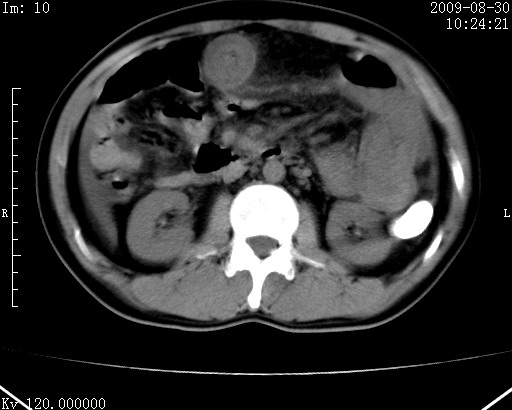

患者唐某,男31岁,已婚,本地务农。

自述入院前两天一次进食较多冷饮之后,出现阵发性上腹部疼痛,次日加剧伴恶心、呕吐,呕吐后症状稍减轻。食欲差。大便每天1-2次,量少,暗红色水样。小便赤。无畏寒、发热、咳嗽等呼吸道症状。无高血压及胃病史。

检查:体温、血压及脉搏正常.皮肤无黄染,浅表无淋巴结肿大。左腹肌紧张,左上腹有压痛,无反跳痛,可触及包块。

生化:钾、钠、氯、钙、ph正常,总胆红素和直接胆红素稍高,空腹血糖稍高。

尿淀粉酶:1256 u/l(正常60-401)。

血常规:wbc 22.4x109/l gr88% ly9.6%其余基本正常。

胃镜:急性胃炎。立位腹平片:未见异常。

下面是ct平扫,降结肠内是对比剂。

术前影像诊断:上段空肠急性缺血性坏死并腹水。建议手术治疗。

术中见上段空肠约70cm长范围坏死,从屈氏韧带远端约10cm处开始。坏死肠管肿胀变形变色,管壁明显环形增厚,部分聚成大肿块,无扭转和套叠。肠系膜上动脉分支内广泛泥沙状血栓。肠切除。

临床诊断:肠系膜上动脉梗塞并急性肠坏死。

开始时我们科也有人认为是套叠,最后统一意见,不考虑肠套。我们看到的“靶征”,“晕圈征”,“双圈征”实际上只是单根肠管的横断面。坏死肿胀后肠壁各层的密度不一样。

左侧腹小肠腔管壁明显增厚,部分内示靶征,走行异常,部分肠系膜绳样改变,肝包膜下及肠间较多液体密度,然梗阻近端肠腔积气不明显。

考虑;肠扭曲伴肠坏死。